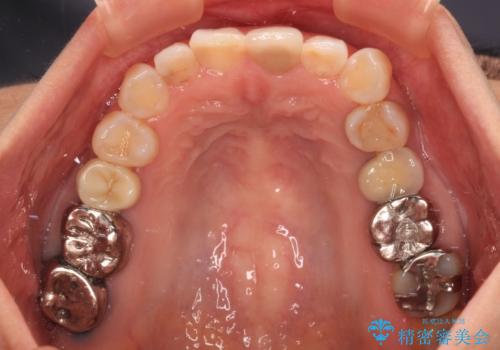

当院では治療前の歯列が整っていない限り、下顎前歯の舌側をワイヤーで固定するようにしています。下顎のみの部分矯正としたことで、マウスピース保定の負担を軽減することができました。

上顎は、失活して歯の色が変色しているため、将来的に補綴治療で自然な口元に仕上げていきたいとのことでした。